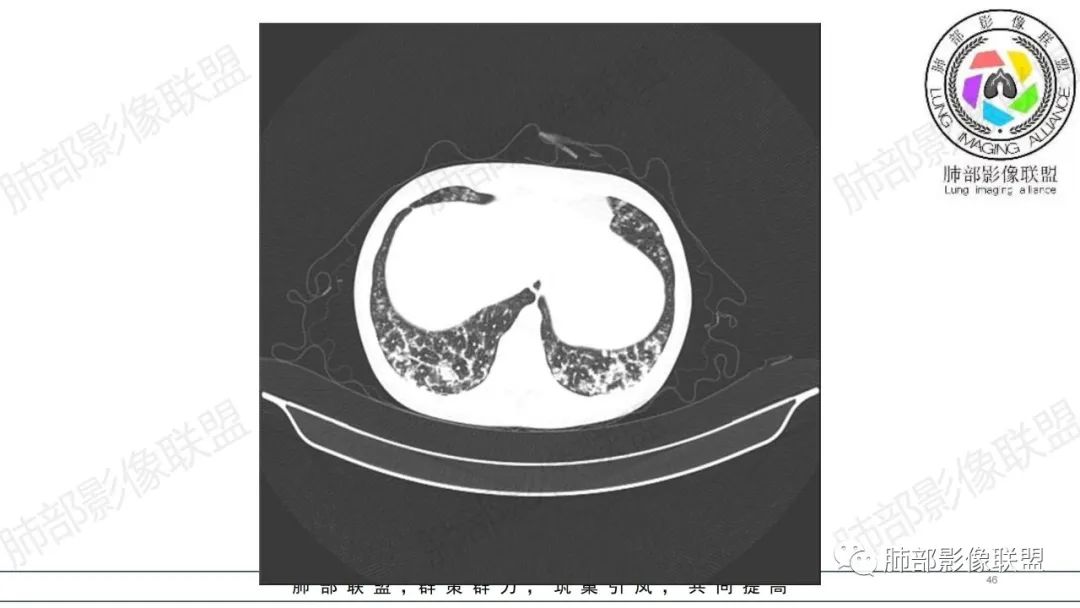

34岁女性患者,“哮喘”病史30年,近期有可疑刺激性气体吸入史;因乏力半年,咳嗽、憋气、发热4天就诊;6.1CT提示双肺广泛毛玻璃影及粟粒样结节,胸膜下闲置及血管周闲置,可见树丫征,部分小叶间隔增厚。考虑:1.过敏性肺泡炎,有可疑刺激气体接触史,胸膜下闲置,广泛毛玻璃影,地图样分布,粟粒结节边界模糊,支持过敏性肺泡炎,但糖皮激素治疗效果不佳,且动态复查血常规血红蛋白进行性降低,过敏性肺泡炎 不符合;2.肺含铁血黄素沉积症:患者30“哮喘”病史,可能为肺含铁症状,肺部CT提示双肺弥漫毛玻璃影及粟粒结节影,中下肺明显,肺底部分小叶间隔增厚,近期咳嗽、憋气、发热,血常规血红蛋白进行性下降,考虑肺含铁急性期症状,但临床无咯血症状,肺含铁不典型。综合考虑:肺含铁血黄素沉积症>过敏性肺泡炎。

年轻女性 ,急性喘息发热,肺部影像弥漫磨玻璃密度,部分细小腺泡结节,胸膜下黑线显示,短期复查,病变密度增高,下肺明显,血管周围肺组织累及较少、且逐渐成小叶间隔分布。考虑弥漫肺泡内病变,并经淋巴道转移,下肺比上肺明显,多为免疫细胞功能下肺较强。1.过敏性肺泡炎,有相关病史,三层密度特点、头尾测分布,符合。2 肺泡微石症,多有钙化,且缓慢起病,病程不太符合,放待排。3 吸入相关肺损伤,有病史,疾病演变过程也符合渗出-肉芽肿改变,建议详细询问病史。4 感染性病变,结核?病变气道分布为主,如此弥漫且没有树丫不符合。5.巨细胞病毒,可以磨玻璃 结节 改变,没有免疫缺陷病史。最后考虑吸入所致 1过敏性肺泡炎、吸入性肺损伤 鉴别肺泡微石症。

肺内气腔磨玻璃结节,肝脾肿大,治疗后间质改变,弥漫大B可能